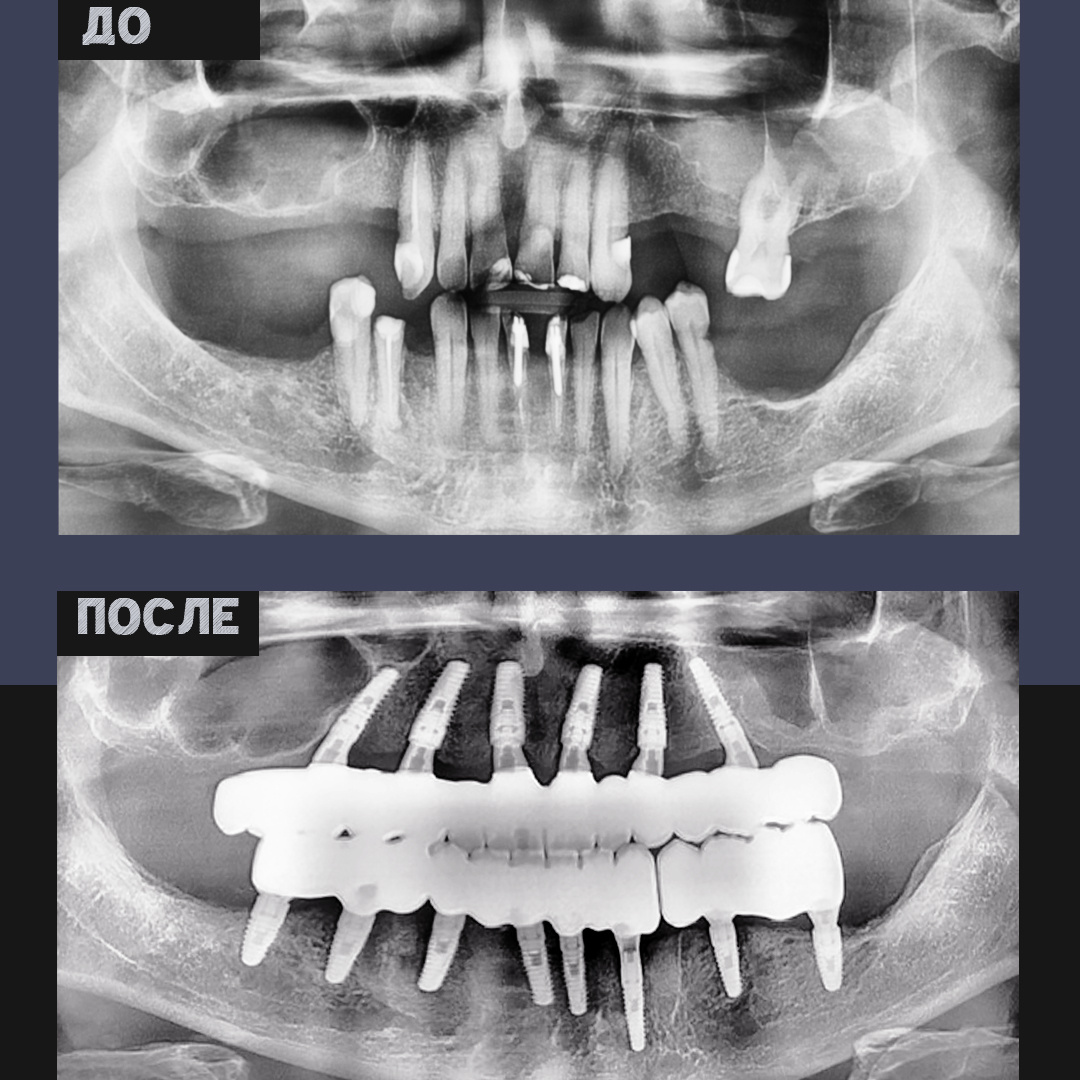

Пациент обратился в NKclinic с жалобами на отсутствие части зубов и трудности при приёме пищи. Диагностика выявила выраженную атрофию костной ткани в области обеих челюстей. При таком состоянии традиционная имплантация невозможна без дополнительных хирургических процедур. Было принято решение о комплексном подходе с применением современных методик реконструкции.

Давид Назаретович Назарян выполнил латерализацию нижнечелюстного нерва — операцию, которая позволяет аккуратно сместить нерв и создать условия для безопасной установки имплантов при недостаточном объёме кости в боковых отделах нижней челюсти.

На верхней челюсти выполнен синус-лифтинг — подъём дна гайморовой пазухи с добавлением костного материала, что обеспечило необходимую высоту кости для стабильной фиксации имплантов.

Пациенту установлено 14 дентальных имплантов:

— по технологии

All-on-6 на верхней челюсти,

All-on-8 на нижней.

Это позволило восстановить весь зубной ряд, обеспечить надёжную опору для мостовидных конструкций, равномерно распределить нагрузку и сохранить форму лица.